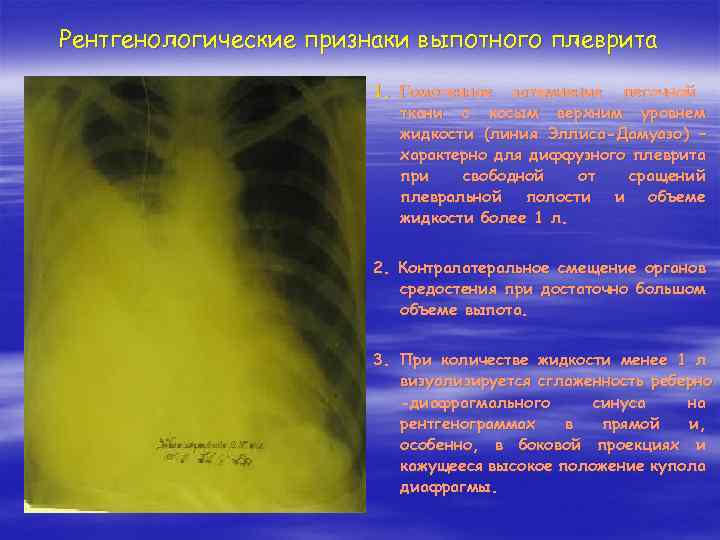

Дифференциальная диагностика заболеваний плевры